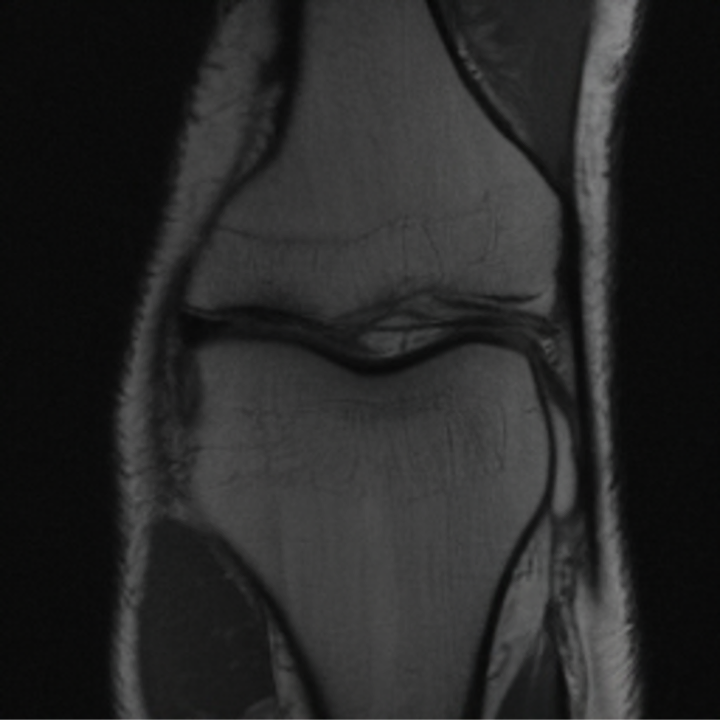

5.3 Out-of-Domain Generalisation

One way to test the generalization capability of the trained X-Diffusion is to test it on a completely different domain from an MRI dataset not seen during training. We report the single-slice results on NYU fastMRI [37, 82], a knee MRI dataset, using the X-Diffusion trained on the BRATS brain MRIs. The results are shown in Figure 9 and Table 2. It shows how successfully X-Diffusion is able to generate knee MRIs from a single image, despite not seeing knees at all in training. To qualitatively assess how realistic our generated 3D volumes were (produced from a single slice), we gave 20 generated examples alongside their real MRI counterparts to an expert orthopaedic surgeon. He was then asked to identify the real example from a given pair. The surgeon identified with certainty only 10 real knee MRIs out of 17, while could not decide on the remaining 3 of the 20 MRI pairs. This further validates the generated out-of-domain MRIs.

In this work, we present X-Diffusion, a cross-sectional diffusion model tailored for Magnetic Resonance Imaging (MRI) data. X-Diffusion is capable of generating the entire MRI volume from just a single MRI slice or optionally from few multiple slices, setting new benchmarks in the precision of synthesized MRIs from extremely sparse observations. The uniqueness lies in the novel view-conditional training and inference of X-Diffusion on MRI volumes, allowing for generalized MRI learning. Our evaluations span both brain tumour MRIs from the BRATS dataset and full-body MRIs from the UK Biobank dataset. Utilizing the paired pre-registered Dual-energy X-ray Absorptiometry (DXA) and MRI modalities in the UK Biobank dataset, X-Diffusion is able to generate detailed 3D MRI volume from a single full-body DXA. Remarkably, the resultant MRIs not only stand out in precision on unseen examples (surpassing state-of-the-art results by large margins) but also flawlessly retain essential features of the original MRI, including tumour profiles, spine curvature, brain volume, and beyond. Furthermore, the trained X-Diffusion model on the MRI datasets attains a generalization capacity out-of-domain (e.g. generating knee MRIs even though it is trained on brains). The code is available on the project website https://emmanuelleb985.github.io/XDiffusion/.

Contributions: (i) We introduce X-Diffusion, a cross-sectional diffusion model that generates MRI slices conditioned on a single input MRI slice or multiple slices. The proposed X-Diffusion achieves state-of-the-art results on MRI reconstruction and super-resolution compared to recent methods on BRATS, a large public dataset of annotated MRIs for brain tumours. (ii) We adapt our X-Diffusion to leverage paired and registered full-body MRI and DXA images from UK Biobank dataset to generate full-body 3D MRI from a single DXA for the first time in the literature. (iii) We validate the generated MRIs on a wide range of tasks that ensure the generated MRIs retain important features of the original MRIs, including tumor profiles, spine curvature, brain volume, and more, without using this meta-information in the generation process. (iv) We showcase the generalization of trained X-Diffusion on different datasets (knee MRIs) illustrating the potential of X-Diffusion to be the first 3D volumetric foundation model in medical imaging.